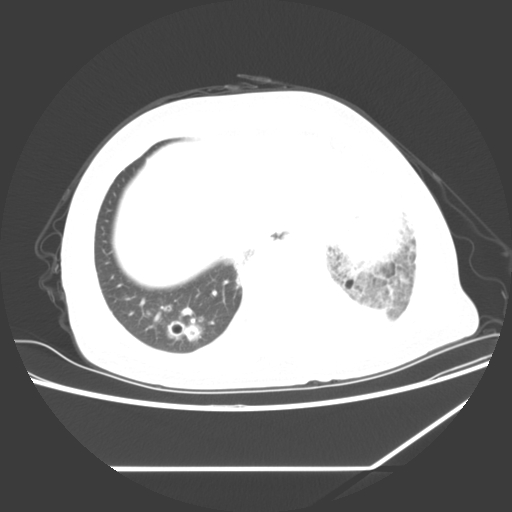

标题: CT25393:病人45岁,咳嗽,吐黄痰带血丝,发热,胸闷月余 [打印本页]

标题: CT25393:病人45岁,咳嗽,吐黄痰带血丝,发热,胸闷月余

1、左肺中央型肺癌并双肺弥漫性转移   2、双肺部感染    3、肺大泡     4、左侧胸腔积液

双侧肺弥漫性病变,可见“空泡征”及“蜂窝征”,考虑肺泡癌可能性大,左侧胸腔积液,考虑胸膜受累可能!

考虑肺泡癌,建议排除感染。

1)不排除肺泡癌可能。2)左侧胸腔积液。